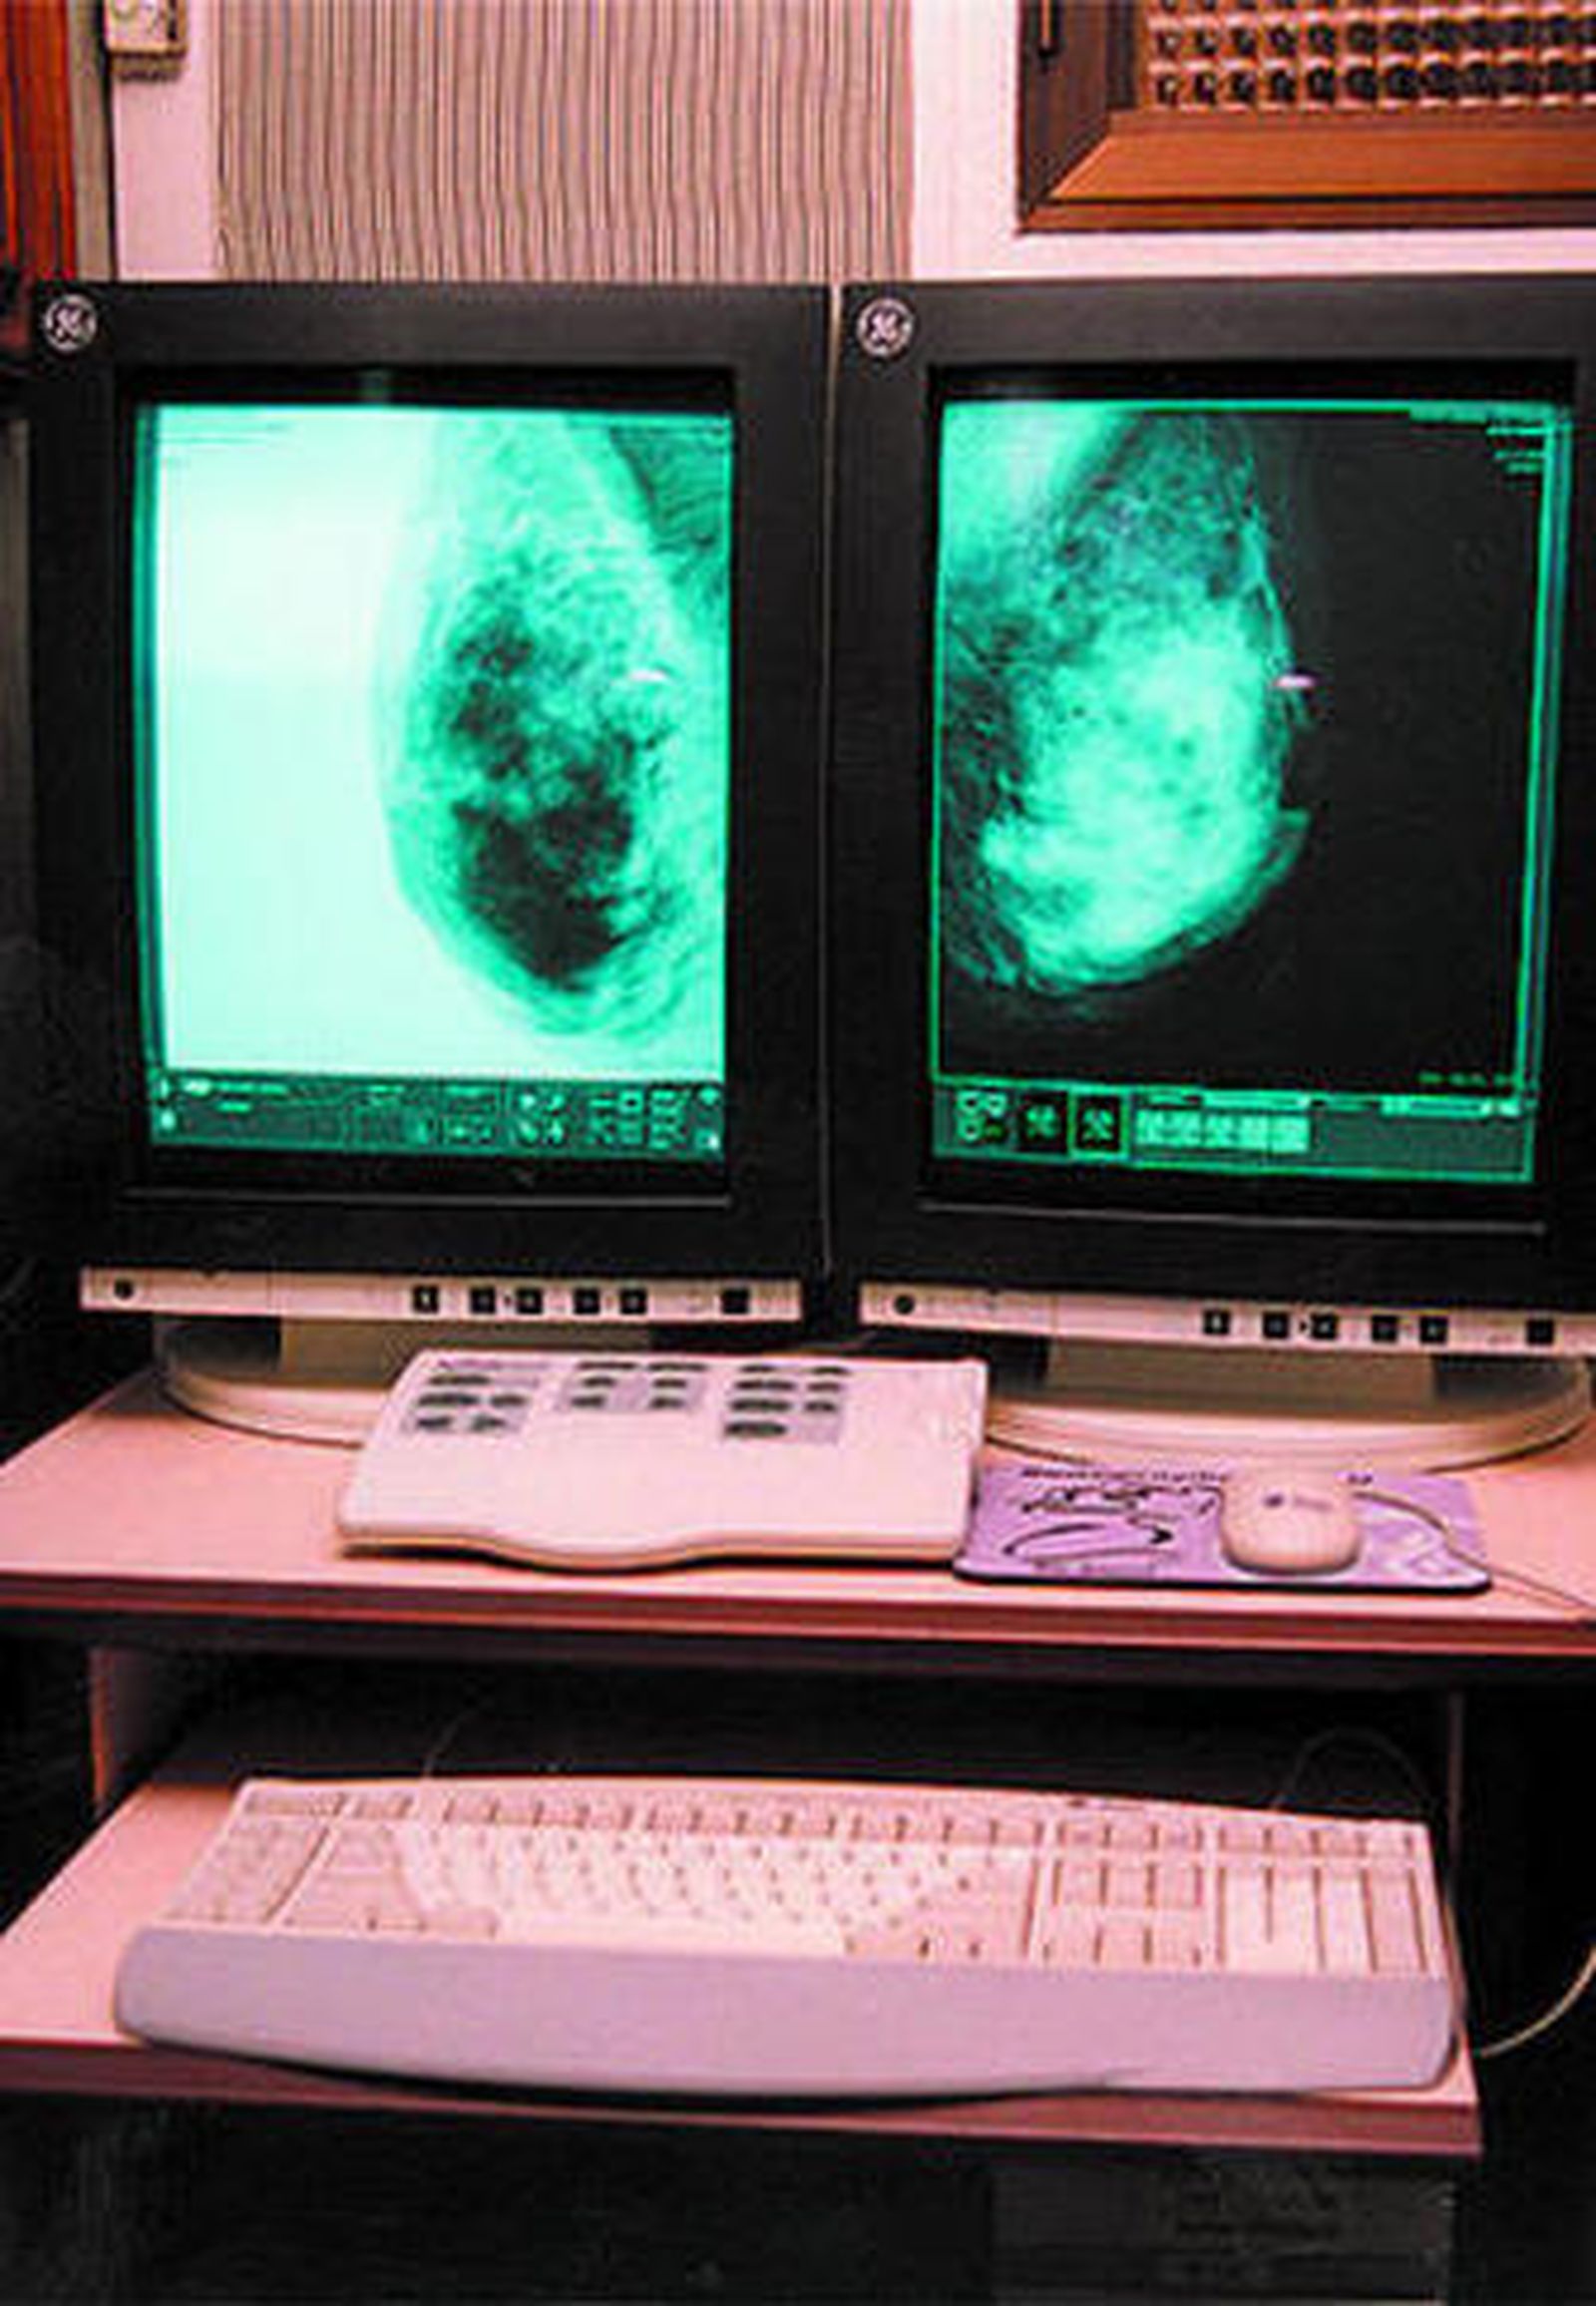

Las mujeres de entre 50 y 69 años de edad del municipio recibirán una cita personalizada mediante carta para realizarse una mamografía en esta unidad móvil que tiene como objetivos detectar los tumores en estados precoces, disminuir la mortalidad por esta patología al menos en un 30 por ciento tras diez años de seguimiento y mejorar la calidad de vida de las mujeres diagnosticadas y tratadas, pudiendo ofrecerles intervenciones menos agresivas.

La metodología seguida es la realización de mamografías en Unidades de Exploración Específicas. Las mujeres que precisan ampliar el estudio diagnóstico o recibir tratamiento serán derivadas al hospital de referencia de la unidad.